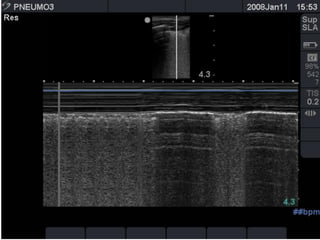

the "seashore sign" (Fig.3).

Absent lung sliding

Exaggerated horizontal artifacts

Loss of comet-tail artifacts

Broadening of the pleural line to a band

The key sonographic signs of

Pneumothorax

Absent lung sliding Exaggeratedhorizontal artifacts Loss of comet-tail artifacts Broadening of the pleural line to a band The key sonographic signs of Pneumothorax